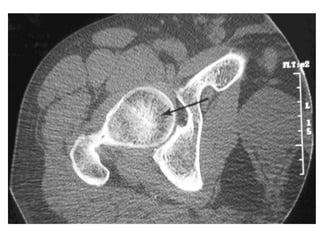

Imaging: CT scan

 Used to assess extent of disease and calcification

 Clearly shows articular deformity

 Calcification and bone collapse

 Central sclerosis in femoral head produces star shaped

structure (asterisk sign)

Imaging: CT scan Used to assess extent of disease and calcification  Clearly shows articular deformity  Calcification and bone collapse  Central sclerosis in femoral head produces star shaped structure (asterisk sign)